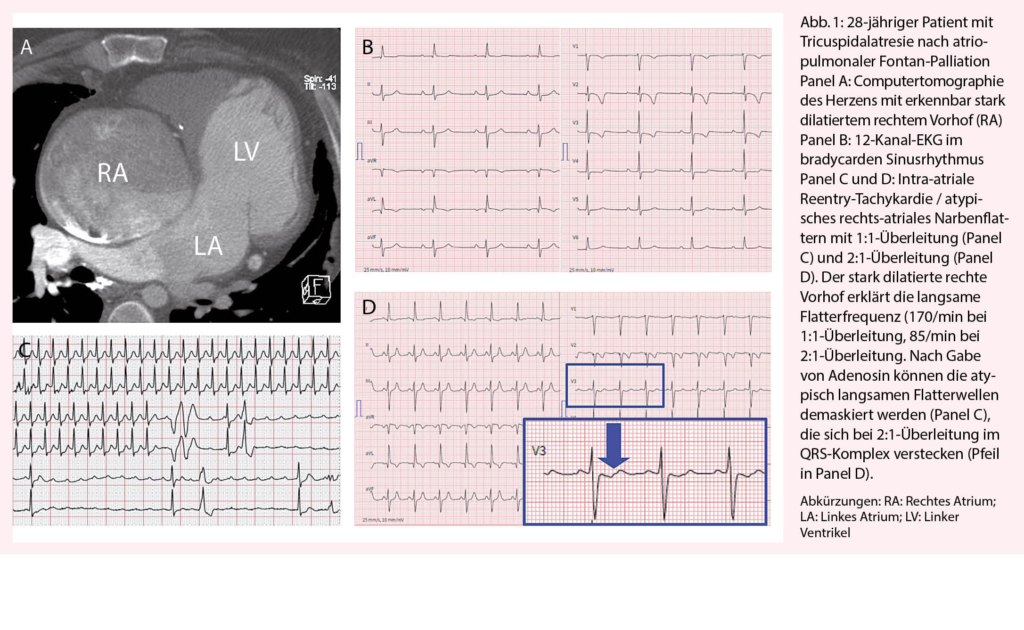

Aufgrund der modifizierten Herzanatomie präsentiert sich das atypische Vorhofflattern (auch intra-atriale Reentry-Tachykardie oder kurz IART genannt) oft ungewöhnlich und wird deshalb nicht selten anfangs verpasst. Insbesondere bei Patienten mit deutlich vergrösserten Herzvorhöfen präsentiert sich das Vorhofflattern mit 2:1-Überleitung oft mit ungewöhnlich tiefer Ventrikelfrequenz (Abb. 1). Gerade der raschen Erkennung des Vorhofflatterns mit 2:1-Überleitung kommt grosse Bedeutung zu! Bei starrer Herzfrequenz über Stunden oder Tage kommt es bei den betroffenen Patienten oft rasch zur Ausbildung einer ausgeprägten Tachy-Myopathie mit schwer eingeschränkter Ventrikelfunktion. So erleben wir im Alltag immer wieder Situationen, bei denen sich wegen der verzögerten Diagnose eines Vorhofflatterns, aus einer eigentlich banalen, gut beherrschbaren Herzrhythmusstörung, ein lebensbedrohlicher Zustand entwickelt. Diesbezüglich kommen einer guten Patientenedukation und einer raschen Abklärung bei Auftreten von Symptomen eine hohe Bedeutung zu.